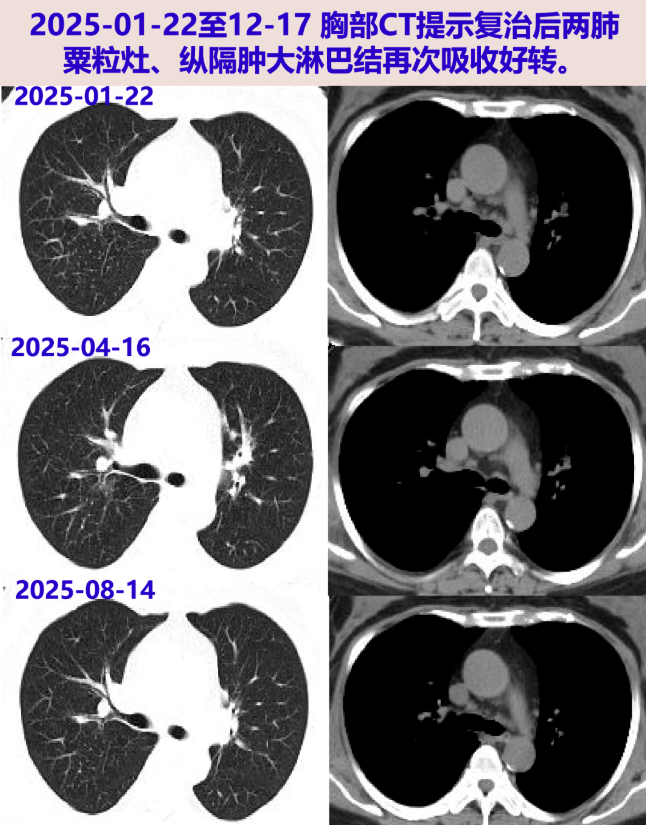

2025-01-22 胸部CT:较24-12-09片肺内病灶吸收,纵隔淋巴结缩小。激素减量方案:甲泼尼龙20mg qd×3周、16mg qd维持。

2025-04-16 胸部CT:较前片好转(最大淋巴结位于左下气管旁19×14mm);炎症指标、ACE阴性;目前甲泼尼龙16mg qd,后续减量方案:14mg qd×2月、12mg qd×2月。

2025-08-14 胸部CT:较前片相仿。后续减量方案:10mg qd×2月、8mg qd×2月。

2025-12-17 胸部CT:较前片相仿。继续甲泼尼龙8mg qd,2~3月后复查胸部CT。